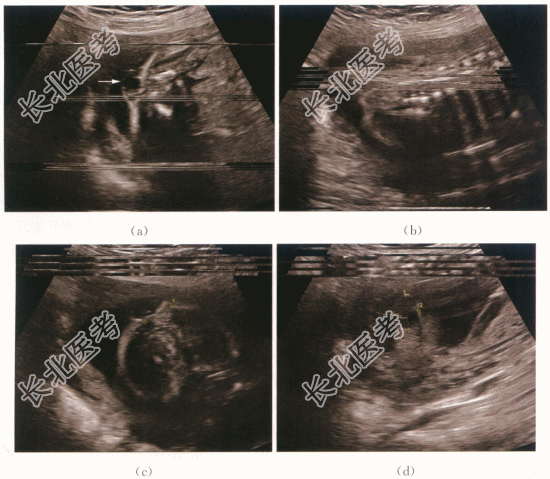

患者,女性,28岁。G₁P₀,孕23周,患者3年前因胎儿脊柱裂引产一次。否认孕期放射性物质接触史、猫狗等动物接触史。既往月经正常,无痛经等不适。

胎儿脊柱裂合并脊膜膨出。